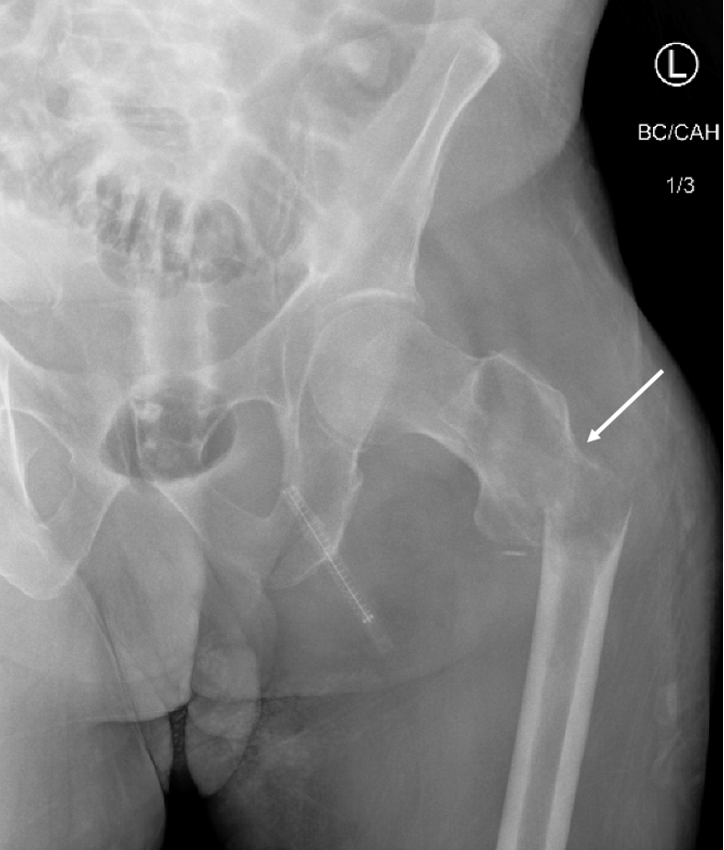

Diagnostic testing. The patient’s initial radiographs from December 2023 demonstrated a lucent lesion (Figure 1) in the proximal femur with cortical thinning, later progressing to a subtrochanteric fracture (Figure 2) and cortical destruction with expansion (Figure 3)1,2, corresponding with biopsy proven fibrous dysplasia with secondary cystic changes.

Figure 2. Plain radiograph of left proximal femur. Progression to displaced pathologic left subtrochanteric femur fracture with cortical destruction (white arrow).